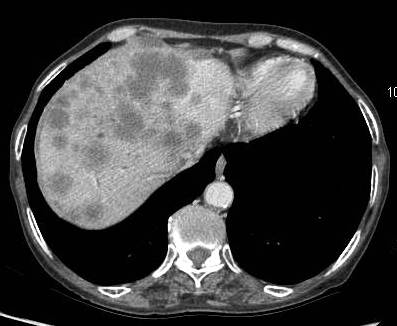

Invasion of hepatic parenchyma

The liver bed is frequently invaded and there is local spread to duodenum, stomach and colon (Figure 6). Liver invasion is suggested by lack of distinct margin between the gallbladder mass and the liver (Figure 7). In a study, the stage distribution according to the TNM system revealed 6, 10, 12, and 53 patients at stages I–IV, respectively. The curative resection rate was 22.2%. Stage-dependent surgical procedures resulted in cumulative survival rates of 33.3%for stages I and II, 8.3% for stage III, and 1.9% for stage IV. The overall prognosis was significantly determined by metastatic spread to the lymph nodes [9].

Figure 6: Advance carcinoma showing the entire liver parenchyma studded with secondaries